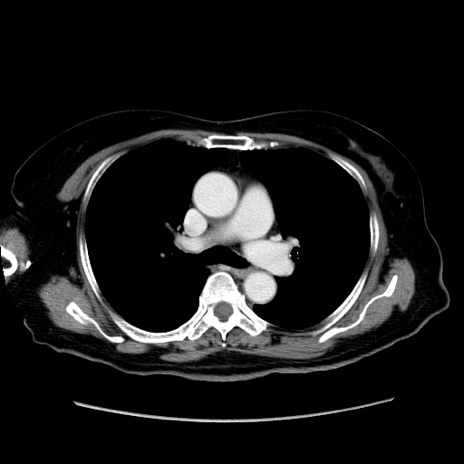

症例19(横断像)

【症例】80歳代女性

【主訴】下腹部痛

【現病歴】約8時間前より下腹部痛の出現あり、救急外来受診。

【既往歴】両側付属器切除

【身体所見】意識清明、下腹部正中に手術痕あり、その部位に一致して圧痛と反跳痛あり。腸蠕動音は亢進。

【データ】WBC 9300、CRP 0.15